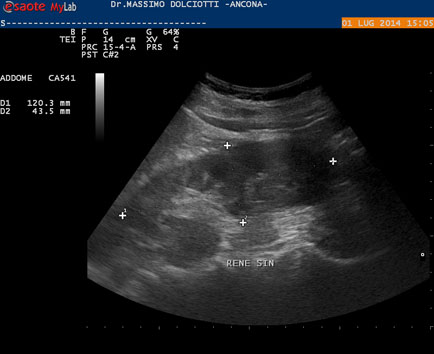

Data Inserimento 20 11 2015 Ecografia Del 20 11 2015 Strumento Esaote Mylab 50 Gold Sonda Convex Multifrequenza 2 5 6 6 Mhz Eta Paziente F 43 Anni Motivazione Dell Esame Riscontro Occasionale Commento All Esame Le Immagini Ed Il Video